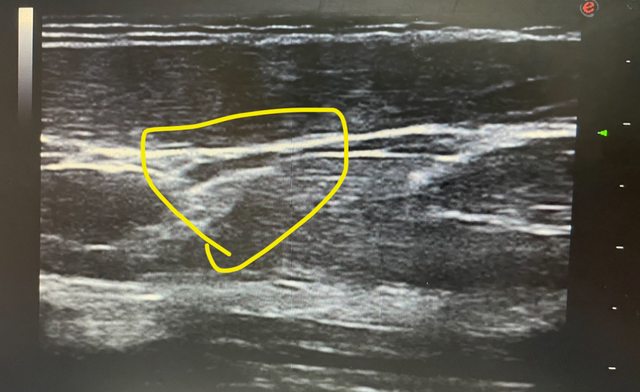

各位好 今天我陪家人去復健科照前臂部位的超音波 醫生看完報告後 說前臂外上髁肌肉拉傷、筋膜剝離 醫生指出超音波圖中有一個白影就是剝離的筋膜 並指出沒有治療方案,醫生也不願意多解釋,只說不能復健,只能等他自己好 想請問板上有人也受過一樣的傷嗎? 是否有較積極的治療方式 我自己在網上找資料也找不到筋膜剝離之類的資料 ——— 附上超音波圖 醫生說黃圈處筋膜跟肌肉分離 https://i.imgur.com/Zx1mcf6.jpg

juor2: 筋膜可能撕裂,但要實際再看看,有時那只是肌肉的一端 01/04 00:12

juor2: 也可能是其他的。如果筋膜有受傷也是可以注射治療的 01/04 00:12

juor2: 只是也要作功能評估才知道是不是這東西所造成 01/04 00:12